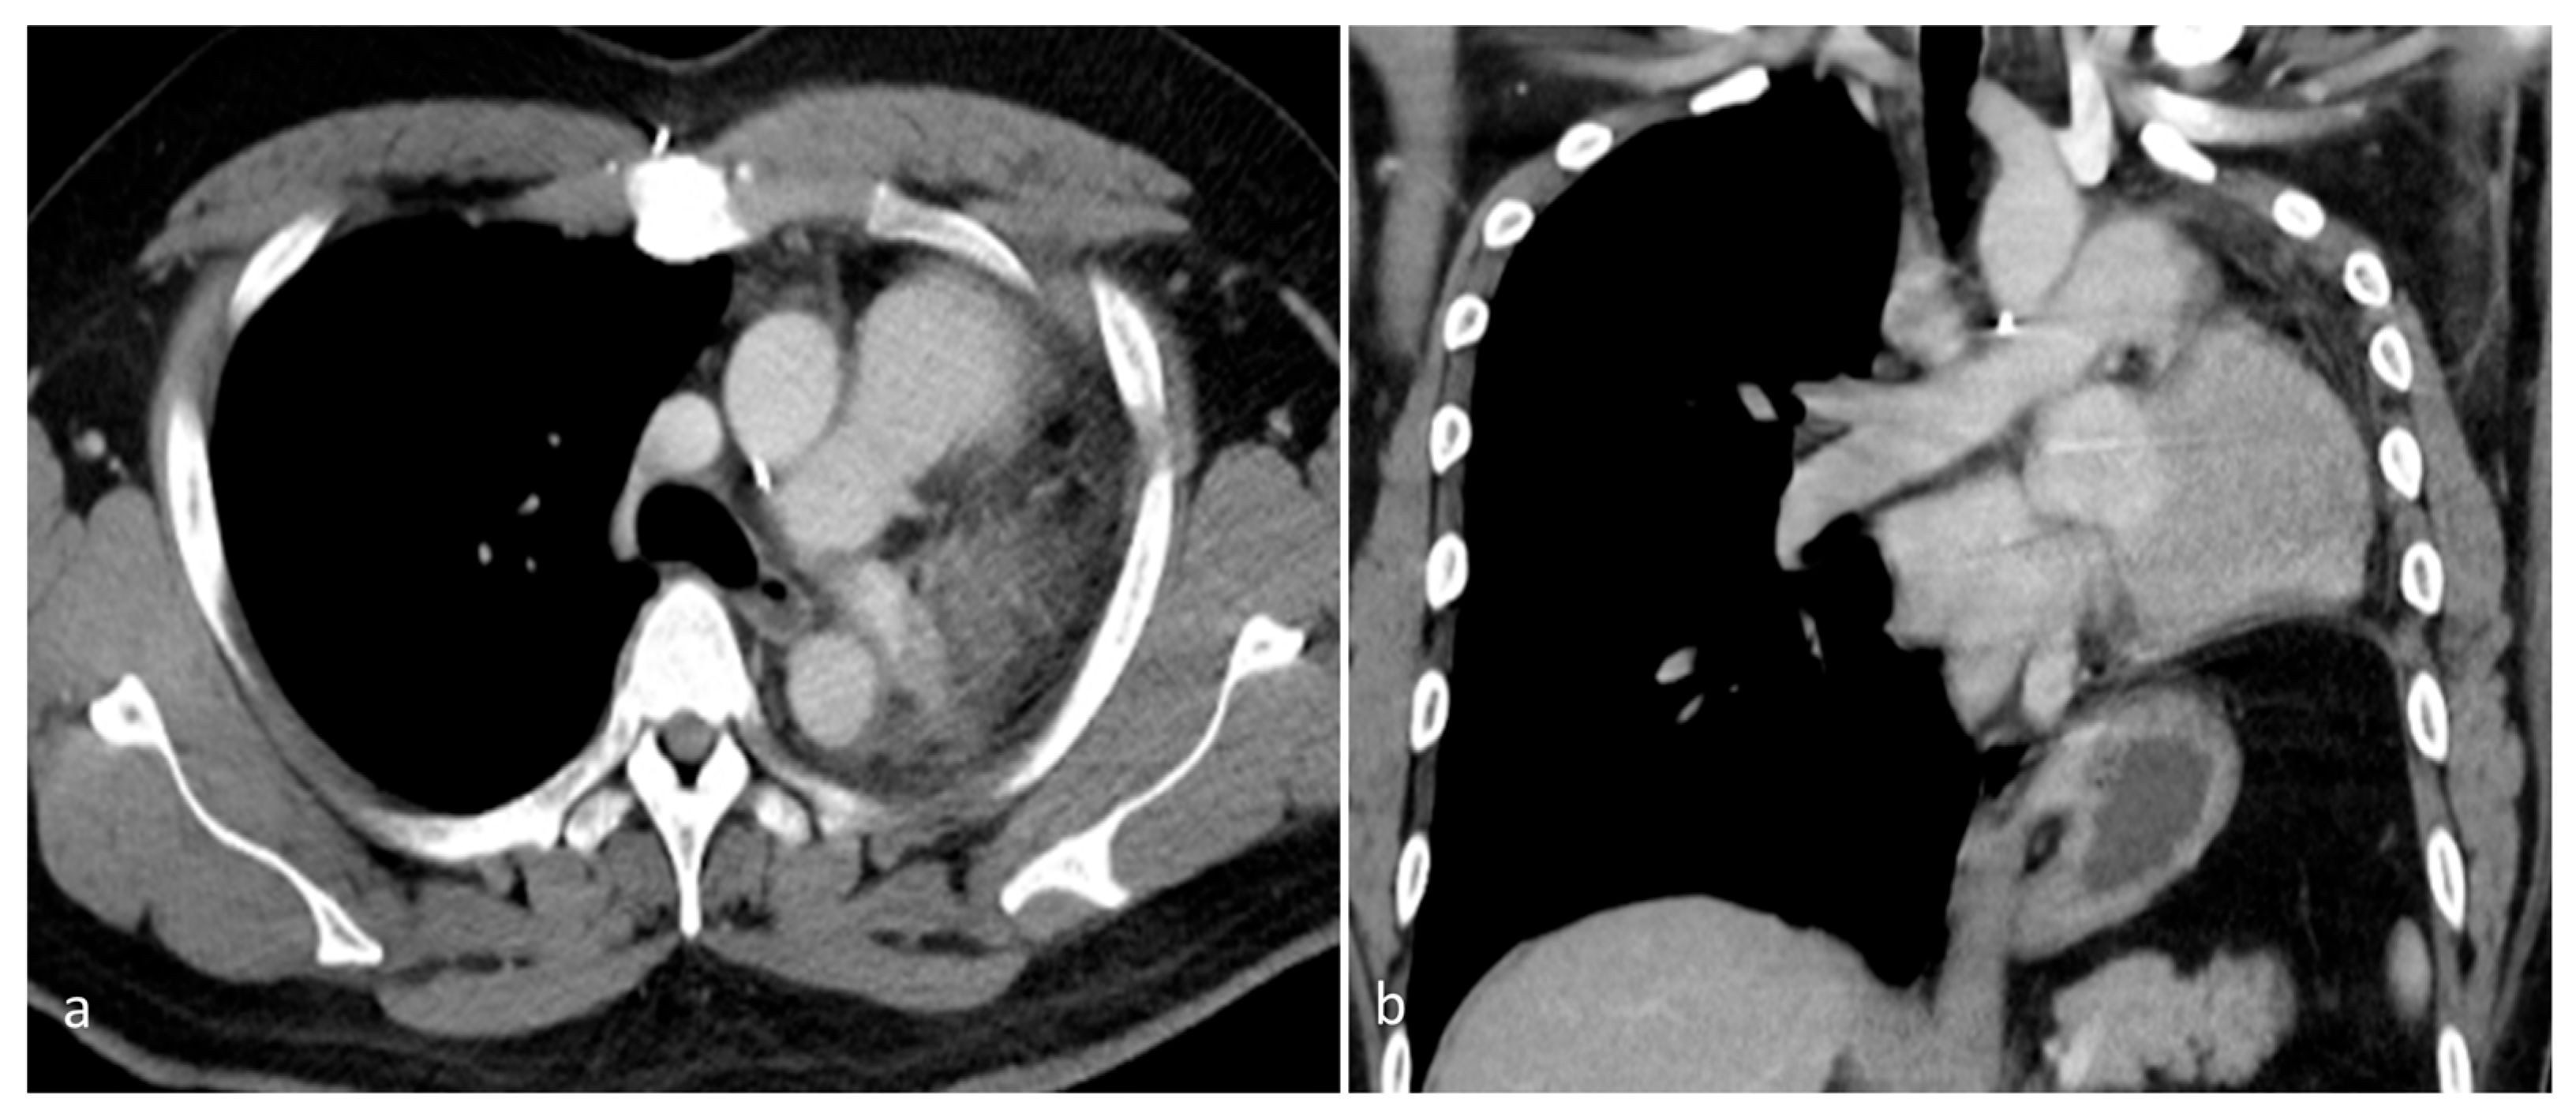

Figure 5. A contrast-enhanced chest CT, performed 2 years after surgery, revealed postoperative changes consistent with prior left pneumonectomy and the complete resection of the left pulmonary artery. (a) Axial view. (b) Coronal view. No residual or recurrent mass was apparent within the left hemithorax. The surgical bed appeared unremarkable, with no signs of local tumor recurrence or the abnormal enhancement of soft tissue. The right lung was well aerated, with no new parenchymal lesions or suspicious nodules. There was no evidence of contralateral lung involvement. No abnormally enlarged mediastinal or hilar lymph nodes were observed. These findings suggest a stable postoperative status with no radiological evidence of disease recurrence over 2 years after surgical resection.